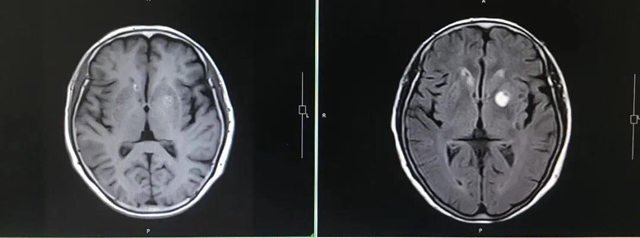

头颅MRI(左:治疗后 右:治疗前)

治疗期间,张婆婆几乎没有腹泻、皮肤疹子等靶向药物的副作用。

1个月后,CT、磁共振复查

张婆婆治疗效果非常好

肺内和颅内病灶基本消失